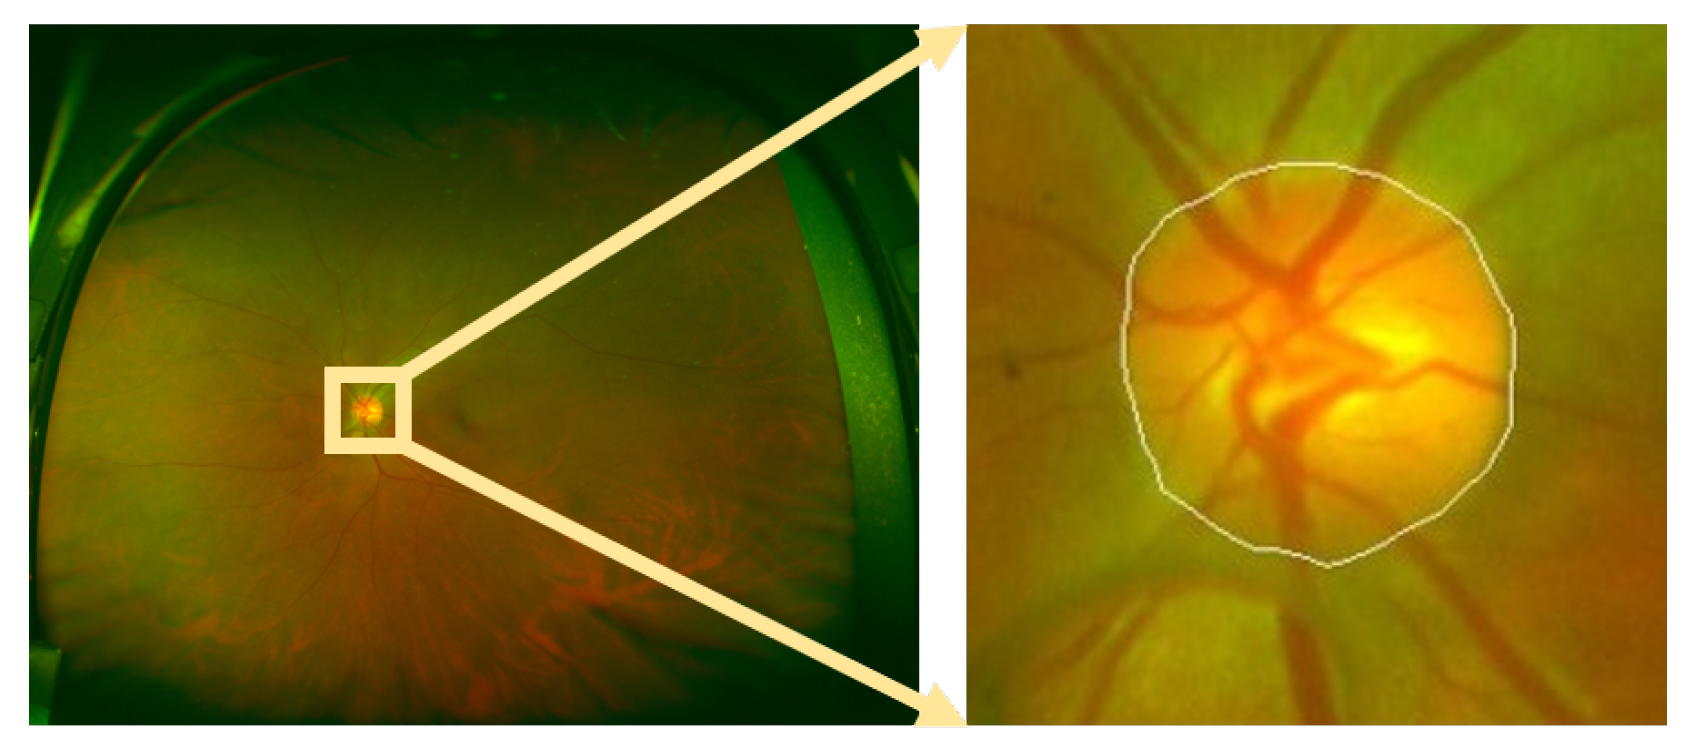

- Different light sources were used when posterior and wide-angle fundus images are taken. Posterior fundus images use white light sources, while wide-angle fundus images utilize red and green light sources. The proposed method utilizes the value channel in the HSV color space to segment the OD. The value channel is the maximal value of the red, green, and blue of these three channels. However, there is no blue channel information in wide-angle fundus images, which may reduce the segmentation accuracy.

- 2.

- The resolution of the ROI on posterior fundus images is about , while the resolution of the ROI on wide-angle fundus images is about . The low resolution of wide-angle fundus images may also be one of the reasons for the low segmentation accuracy.